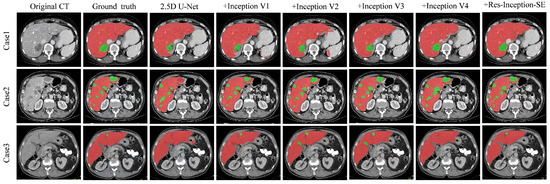

However, limitation still exists for CNN-based techniques to meet the high precision requirement for clinical applications. Figure 1 illustrates the examples of liver and tumor CT images. We can see that, in abdominal CT images, the liver, as well as the lesion region, have low contrast with the surrounding tissues, and a single CT slice provides limited information. The accuracy of 2D analysis methods based on a single CT slice is not satisfactory, although they can achieve high segmentation efficiency. Segmentation methods based on 3D images can fully utilize spatial information to enhance segmentation accuracy, but the parameter of 3D deep learning models are substantially higher, requiring higher computational resources; 2D and 3D segmentation methods are unable to strike a balance between efficiency and accuracy. Furthermore, liver tumors in CT images have different sizes and locations, and their visual features need to be fully extracted to be able to adapt to the changes in tumor size and make the segmentation results closer to the true ground truth.

Figure 1. Examples of liver CT images: (a) tumors located around the liver boundary (b) small and low-contrast liver tumor.